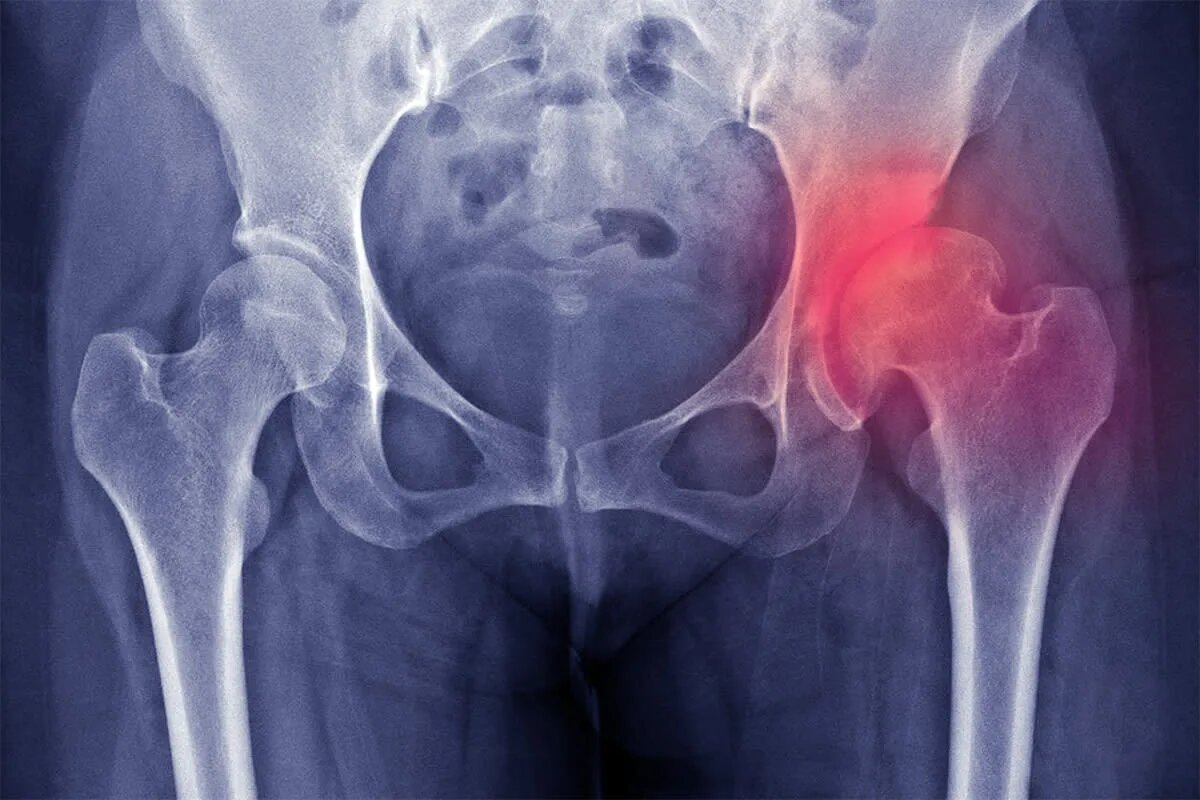

Коксартроз — это форма остеоартроза, затрагивающая именно тазобедренный сустав. При этом заболевании постепенно истончается хрящ, который покрывает поверхности сустава и обеспечивает плавное скольжение костей. Когда хрящ изнашивается, кости начинают тереться друг о друга, вызывая воспаление, боль и формирование костных разрастаний (остеофитов). Со временем сустав деформируется, а движения становятся всё более ограниченными.

Хотя точный диагноз ставит врач по рентгену или МРТ, ориентироваться в симптомах важно каждому:

• Рентген показывает почти полное исчезновение хряща.